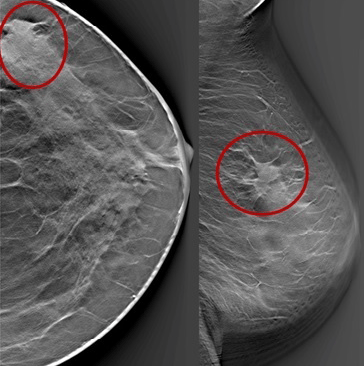

Mamografi (Altın Standart):

Mikrokalsifikasyonlar: LR (+) 15.0. (Özellikle pleomorfik/dallanan tipteyse)

Spiküle Kitle: LR (+) > 20.0.

"Mamografide Spiküle (Dikenli) Kitle Varlığı ile Luminal A Alt Tip Meme Kanseri Arasında Bir Korelasyon Var mıdır?"

Bu çalışma, mamografik görüntüleme bulguları ile meme kanserinin moleküler alt tipleri arasındaki biyolojik bağı incelemektedir. 317 hastanın retrospektif analizi üzerinden yapılan çalışma, fenotip (görüntü) ile genotip (moleküler belirteçler) arasındaki ilişkiyi Bayesyen bir olasılık çerçevesinde sunar.

1. Temel Bulgular ve İstatistiksel Veriler

Luminal A Dominansı: Spiküle (kenarları ışınsal uzantılı) kitlelerin %71'i Luminal A alt tipi olarak sınıflandırılmıştır.

Olasılık Oranı (Odds Ratio): Luminal A alt tipindeki kitlelerin, diğer alt tiplere oranla mamografide spiküle görünüm sergileme olasılığı 10.3 kat daha fazladır (p < 0.001).

Biyobelirteç Korelasyonu: Spiküle görünümün en güçlü öngörücüleri Düşük Ki67 indeksi (< %14) ve HER2 negatifliğidir. Hormon reseptör (ER/PR) pozitifliği de ilişkili bulunmuştur ancak etkisi Ki67 ve HER2 kadar baskın değildir.

2. Klinik ve Prognostik Çıkarımlar

İyi Prognoz İşareti: Spiküle marjlar, genellikle tümör hücrelerinin çevre dokuyla (stroma/yağ dokusu) etkileşimini ve düşük dereceli (low-grade) progresyonu gösterir. Bu durum, spiküle kitlelerin neden daha iyi bir prognoza işaret ettiğini açıklar.

Tanısal Doğrulama: Eğer bir tümör mamografide spiküle görünüyorsa ancak patolojide "HER2 pozitif" geliyorsa, bu bir uyumsuzluk (discordance) bayrağıdır; testin tekrarı düşünülebilir.

3. Sonuç

Mamografide görülen spiküle kitle, invaziv meme kanserinin Luminal A alt tipi için güçlü bir radyolojik belirteçtir. Bu korelasyonun temelinde tümörün düşük proliferatif aktivitesi (Ki67) ve HER2 gen ekspresyonunun olmaması yatar. Bu veriler, "spiküle kitle" verisinin, biyopsi öncesi Luminal A olasılığını (prior probability) belirgin şekilde yükselttiğini kanıtlamaktadır.